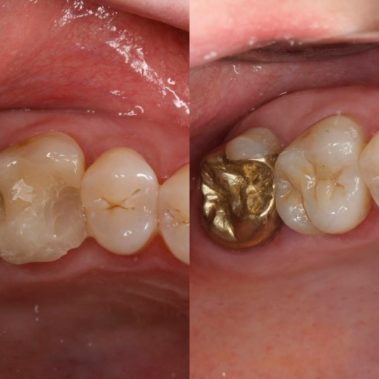

Unser hochqualifiziertes Praxisteam aus Zahnärzten und Mitarbeiterinnen steht Ihnen mit Achtsamkeit, Vertrauen und Professionalität in Kemnath zur Verfügung.